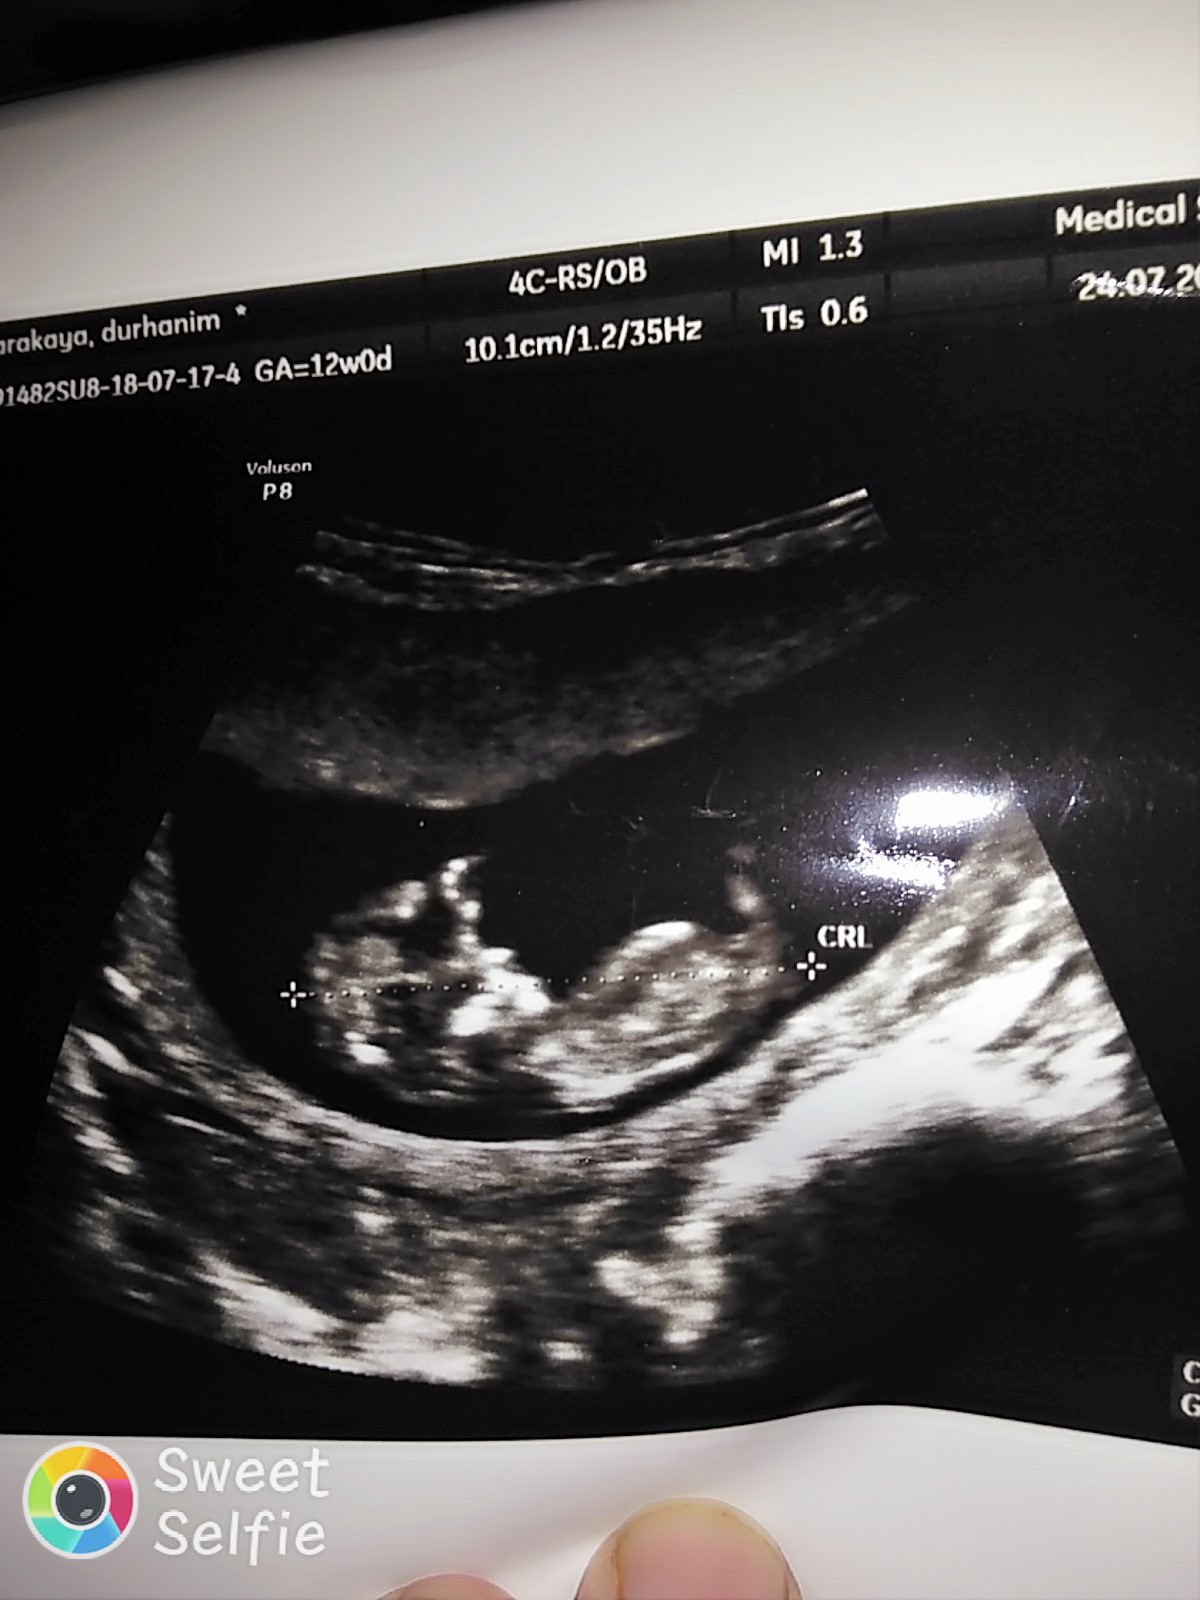

Nub teorisiyle cinsiyeti uzman hekimler belirleyebiliyormuş. Bu yüzden doğruluk payı var.

Nub teorisi ile ilgili istatistiki bilgiler şöyledir;

1 hafta sonunda, doğruluk oranı 48 yüzde olduğu

12 hafta sonunda, doğruluk oranı 91 yüzde olduğu

13 hafta sonunda, doğruluk oranı 94 yüzde olduğu